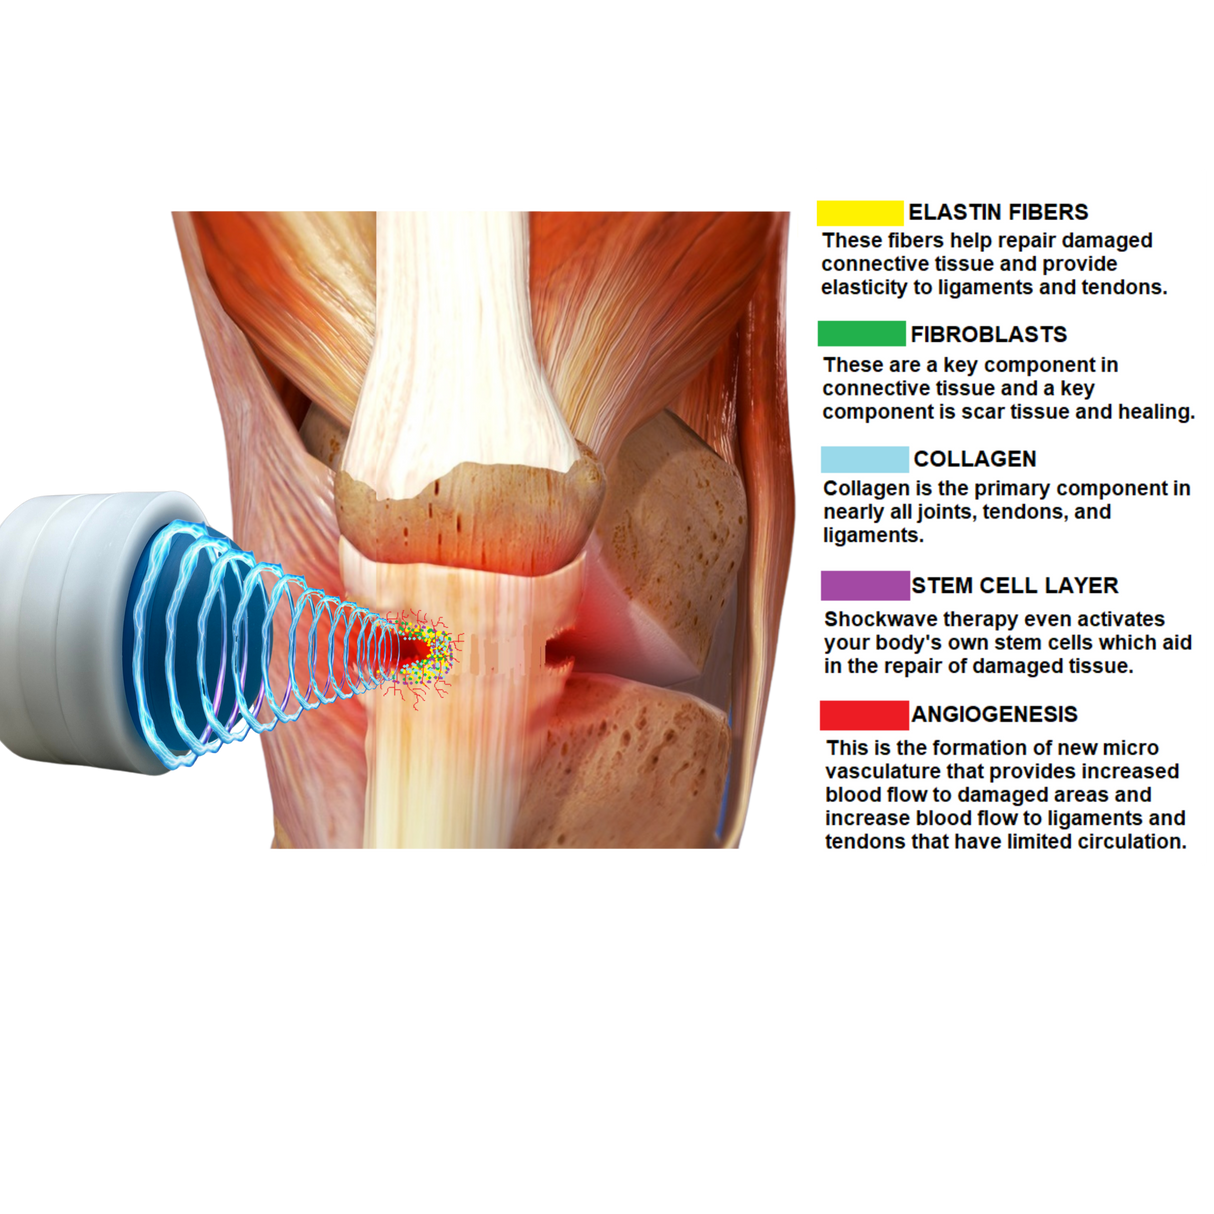

Meet Pulse Wave™—the 4th Generation Focused Shockwave Therapy Machine designed to revolutionize pain management, accelerate recovery, and deliver a rapid return on investment for clinics and sports medicine facilities. Built with advanced electromagnetic technology, Pulse Wave™ provides 100% focused energy to target deeper tissues with minimal discomfort and zero maintenance requirements.

Electromagnetic Precision:

Eliminates spark-gap inefficiencies, delivering consistent pressure for deeper penetration. -